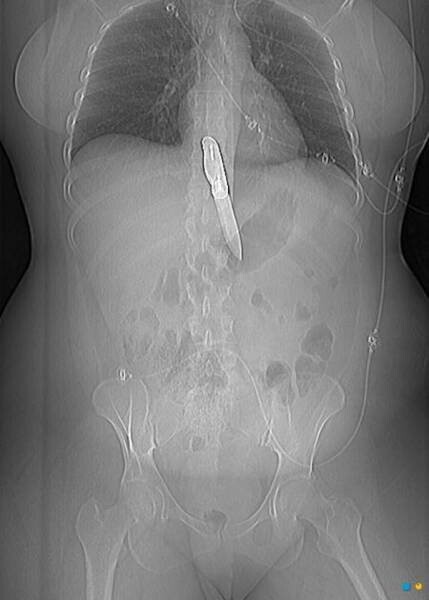

7. Нож